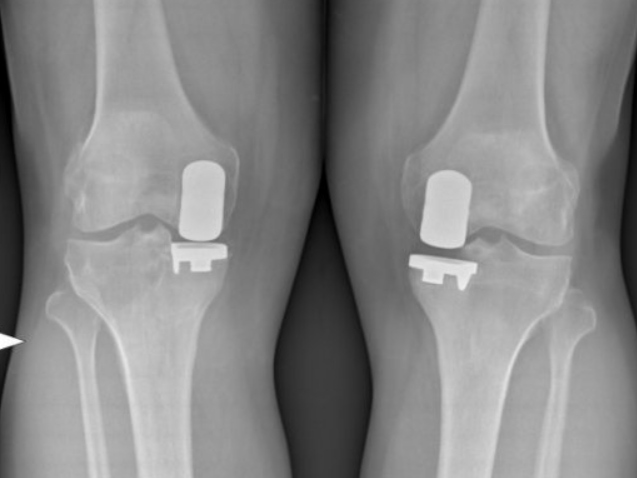

Qu'est-ce qu'une Prothèse uni-compartimentale de Genou?

Cette intervention consiste à remplacer une partie de l’articulation du genou, le compartiment fémoro-tibial interne ou externe, par des composants artificiels qui reproduisent l’anatomie initiale du genou. Le type d’implant doit être adapté à chaque cas particulier, en ce qui concerne sa forme, sa taille, la nature des matériaux entrant dans sa composition, son revêtement extérieur et la technique chirurgicale à employer.

Généralement, une prothèse de genou se divise en deux parties : un insert fémoral et une embase tibiale surmontée d’un polyéthylène. Les composants sont généralement fixés par du ciment.

Album photo